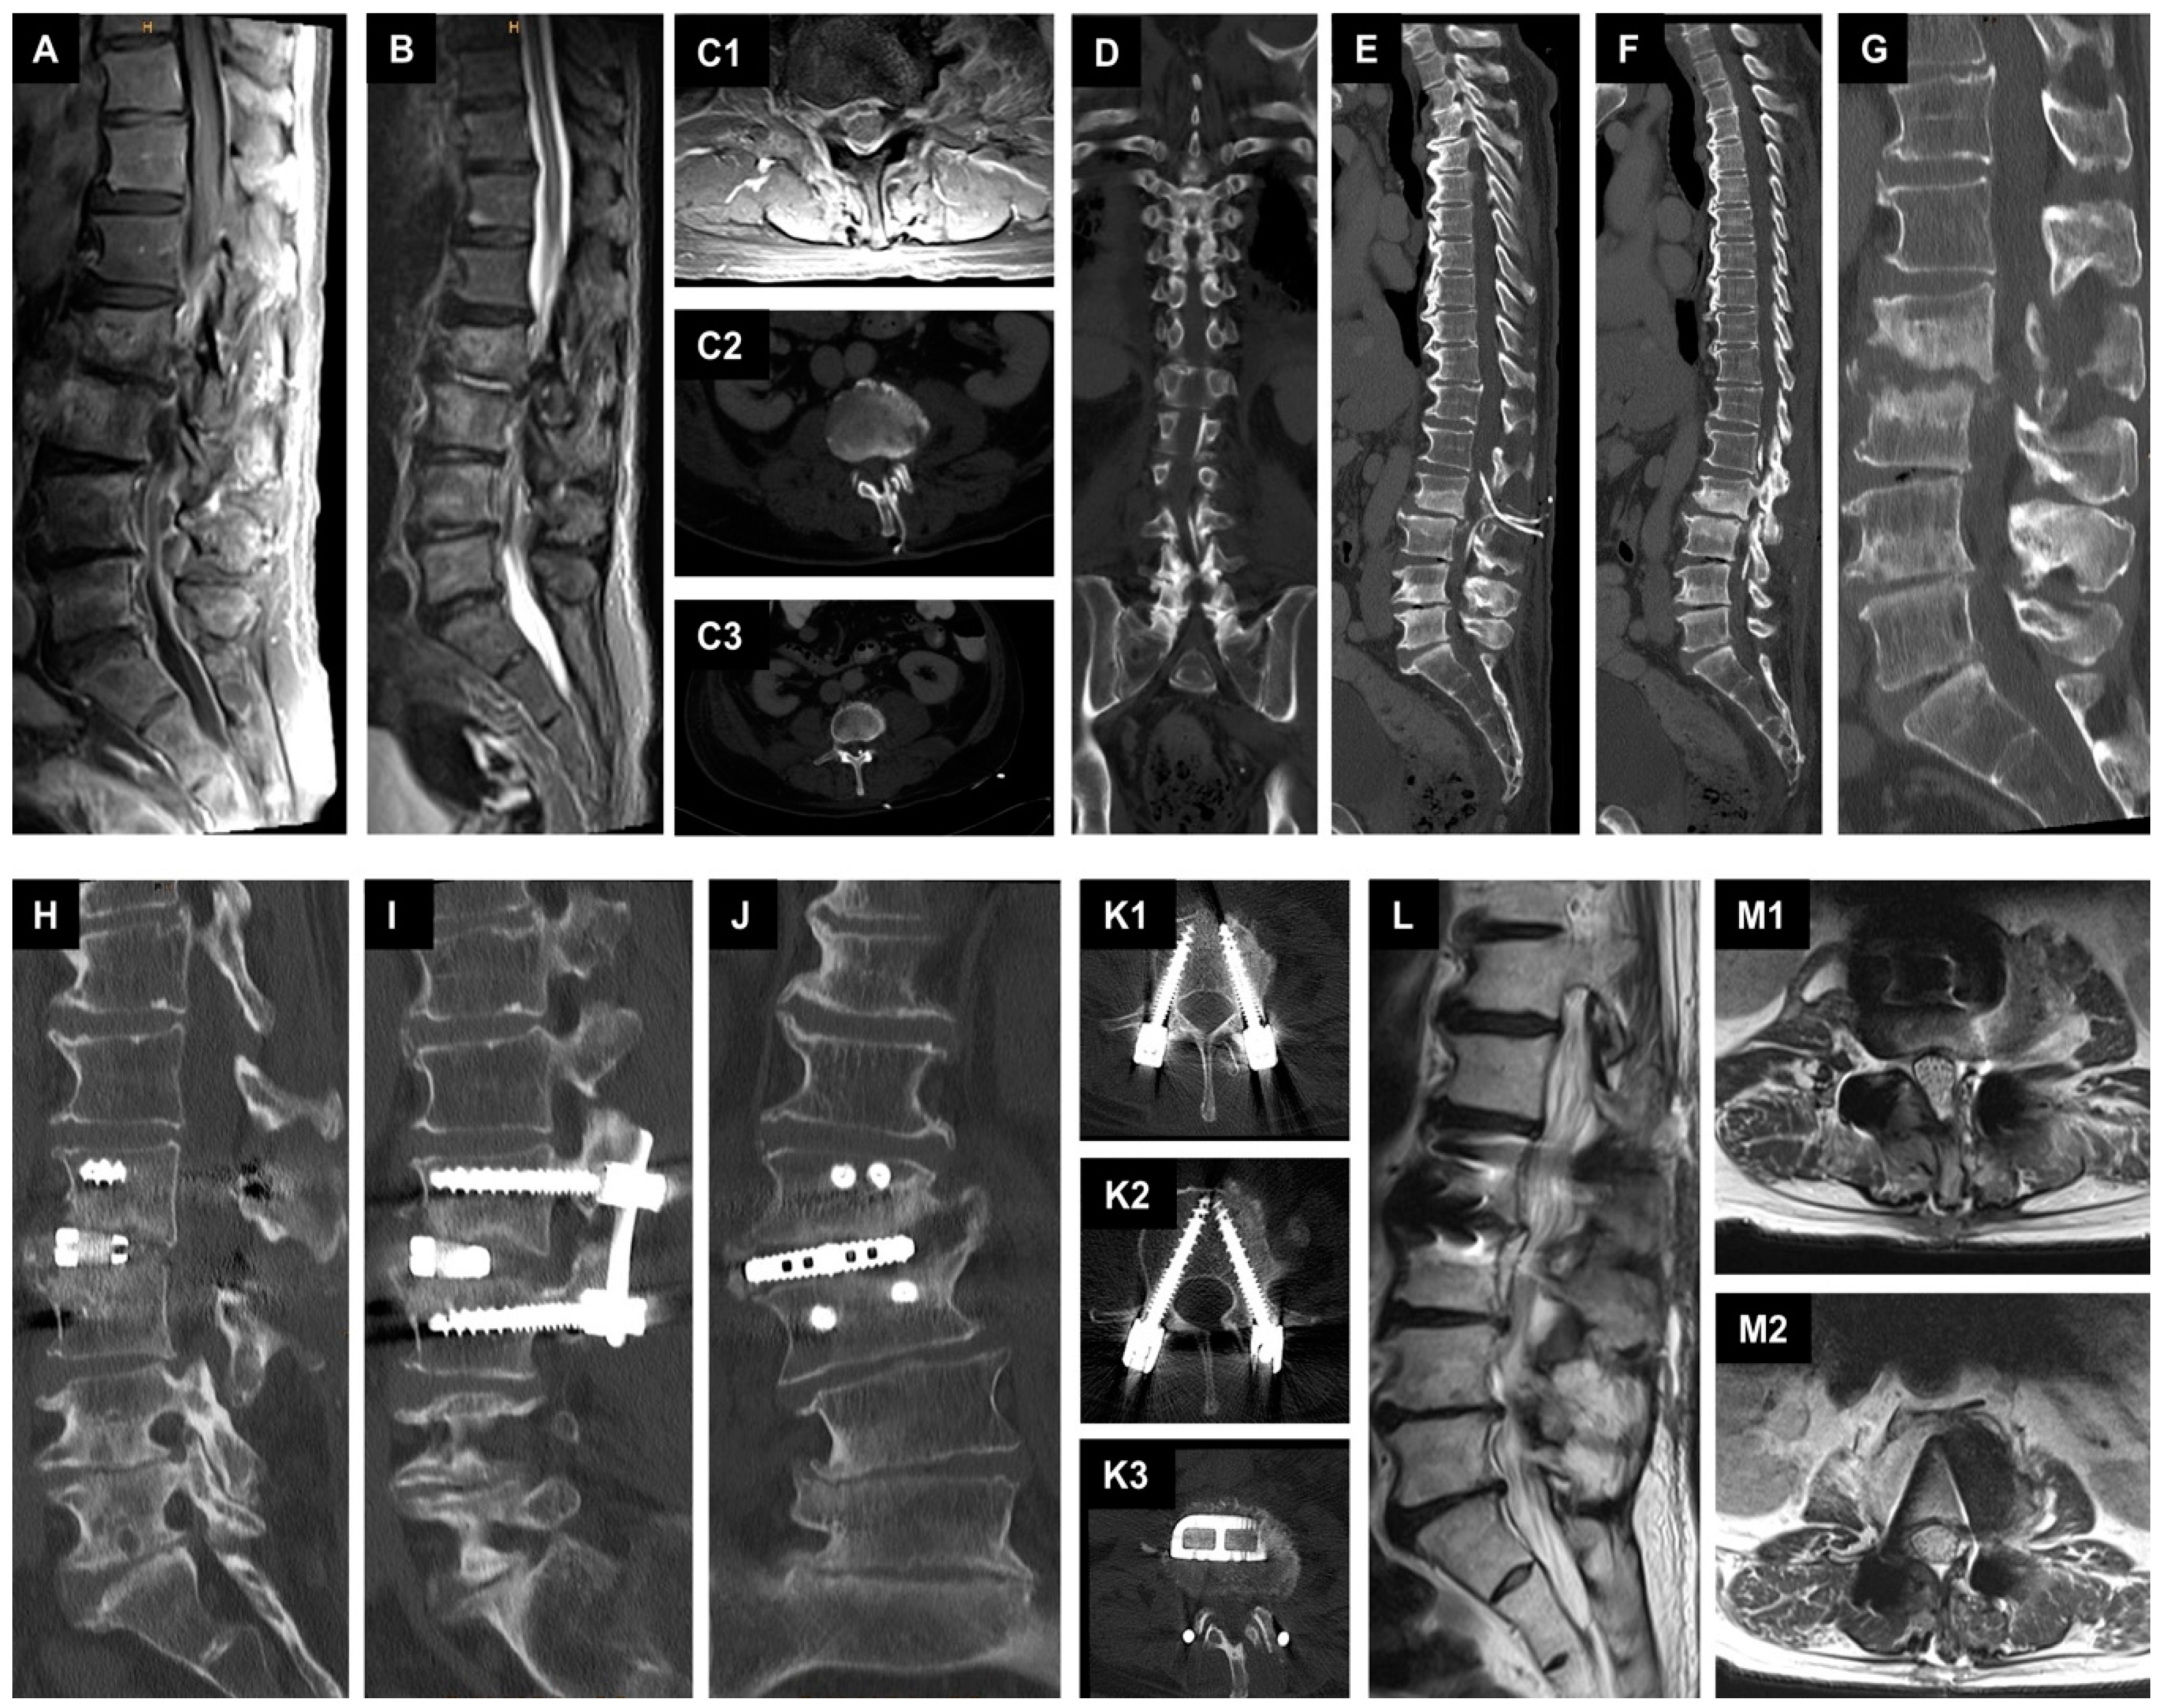

2.3.2. Second Case with Spondylodiscitis and Epidural Empyema